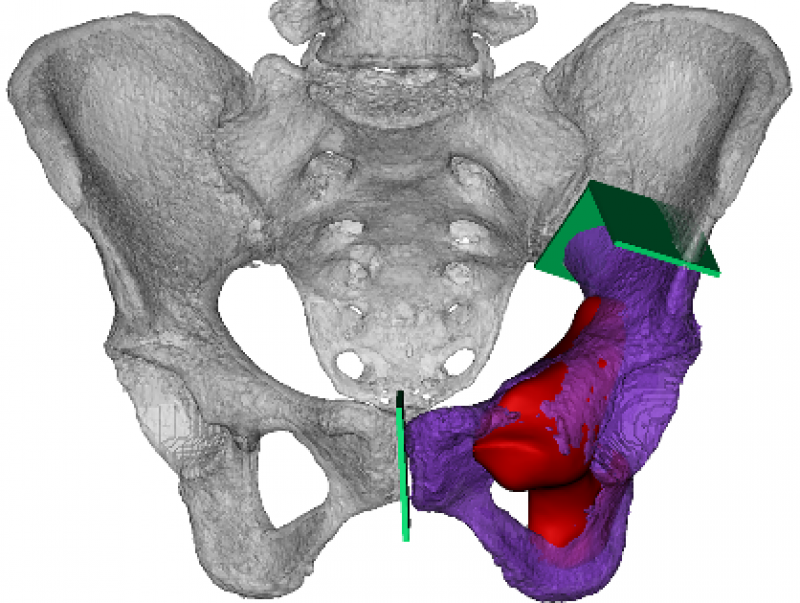

假体均由四川大学华西医院骨与软组织肿瘤中心临床团队设计并由企业制造。个性化模拟正常的尺寸和外观是假体设计和制造的主要原则。将CT数据导入Mimics V20.0 (Materialise Corp.,Leuven,Belgium)中建立虚拟三维模型,此后,利用图像融合技术将MRI数据整合至虚拟三维模型中用以显示肿瘤边界(图5)。